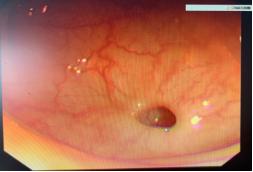

女性,62岁,因“腹痛腹胀2月余,加重2天”入院。患者2月前无明显诱因下出现腹部胀痛,无恶心呕吐,无发热恶寒,于外院查肠镜示克罗恩病,予以美沙拉嗪联合沙利度胺保守治疗,病情逐渐好转;2天前患者腹痛加重,呈胀痛、伴恶心欲吐,无发热恶寒,遂于外院查全腹部CT提示回盲部穿孔,为求进一步治疗,遂来我院就诊。入院时查体,腹部平软,右下腹稍有压痛,无反跳痛;入院诊断为克罗恩病伴回盲部穿孔;入院后急查腹部CT提示肝周少量游离气体、回盲部增厚(图4-1);患者入院腹部症状较轻,考虑穿孔范围较小,且被穿孔周围网膜紧紧覆盖,未破溃入腹腔内,未见明显腹腔感染迹象,故予保守治疗,经治后患者病情好转,复查CT提示未见明显腹腔游离气体。10天后好转出院,出院后继续予以美沙拉嗪联合沙利度胺控制病情,6月后于我院行有半结肠切除术,治愈出院。